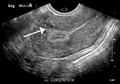

A relatively large submucosal leiomyoma; it fills out the major part of the endometrial cavity